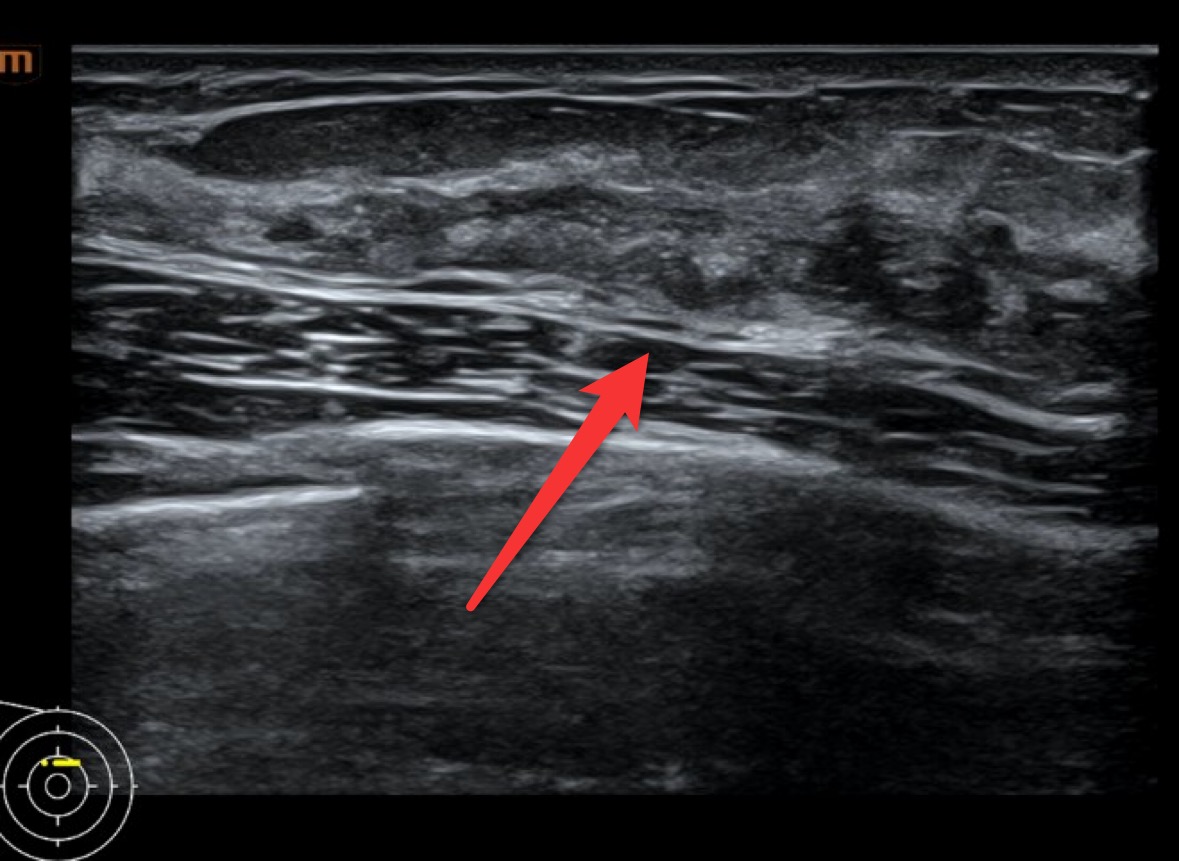

它怕“小透明”。 B超对某些类型的癌不敏感,比如那种只在导管内密密麻麻长着微小钙化的原位癌。那些钙化点像针尖一样小,B超的“相机”分辨率不够,拍不清楚。这时候,就得请出另一位侦探——乳腺钼靶,它可是捕捉钙化的专家。所以有时候要“组合出警”,才能不放过坏蛋[2]。

这名患者彩超并未见明显的结节,仅表现为局部回声异常(标记处可见异常回声),彩超BI-RADS分级0类